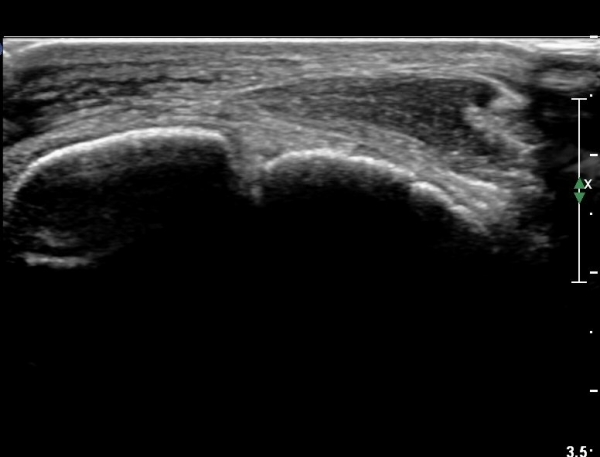

¹ß¸ñ À§¿¡¼­ ¸»´Ü ¾ÕÂÊ °æ°ñºñ°ñÀδë Á¾´Ü¸é°Ë»ç¿¡¼­ ƯÀÌ ¼Ò°ßÀ» º¸ÀÌÁö ¾Ê´Â´Ù(»çÁø 2, 3).